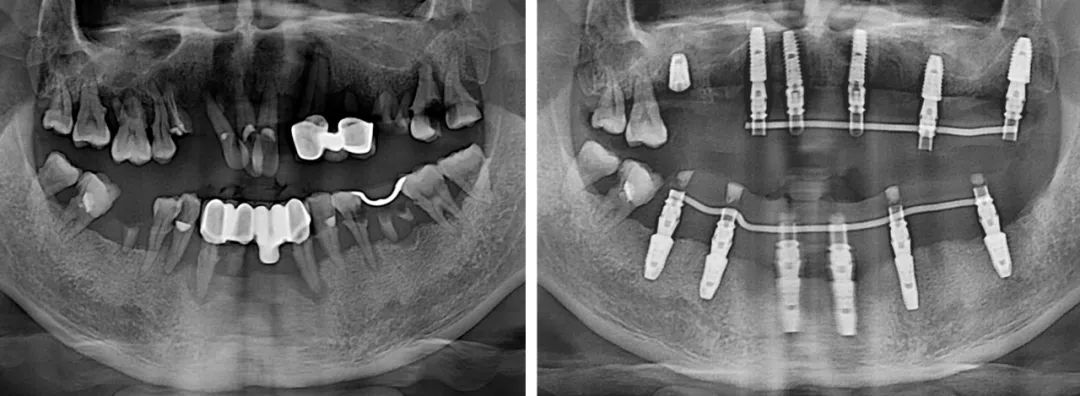

短短幾年,劉今朝已完成種植修復治療上千例,成長速度比絕大多數同齡醫生更快。工作以來,他已多次公派參加專業培訓和學術會議,同時,也完成了從常規種植到半口全口無牙頜種植的技術進階。

“做種植牙,良好的咬合是最終目的。相對單顆、多顆種植,半口咬合重建難度更大。半口種植的患者往往對側牙齒也不是特別好,種植后如何調整咬合,非??简炨t生的水平。”

技術進階,意味著難度也有了進階,不管遇到什么樣的病例,劉今朝始終牢記“修復是種植的目的”這一原則,以最終的修復效果為目標,來指導整個治療。